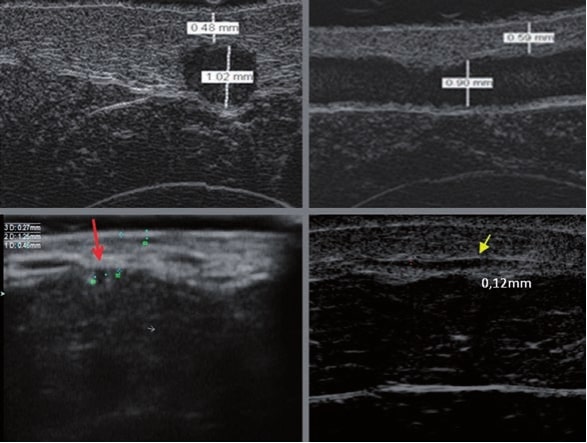

Gefäßveränderungen an den Beinen stehen in Zusammenhang mit Anomalien im oberflächlichen Venensystem oberhalb der Faszie. Die Ätiologie dieser Störungen ist komplex. Zu den häufigsten Ursachen venöser Störungen gehören genetische Faktoren, hormonelle Einflüsse, Adipositas, Lebensstil und Schwangerschaften. Diese Faktoren führen zu einer Insuffizienz der Venenklappen und Perforatoren, wodurch sich Blut in den Gefäßen staut, venöser Hochdruck entsteht und eine Gefäßerweiterung resultiert. Im oberflächlichen Venensystem unterscheidet man zwei Hauptvenen: die Vena saphena magna und die Vena saphena parva sowie zahlreiche Verbindungsvenen (Perforatoren) und kleine Blutgefäße (3). Um die Gefäße des oberflächlichen Venensystems zu systematisieren, ist es sinnvoll, eine Klassifikation zu verwenden, die fünf Gefäßtypen unterscheidet (4). Typ I umfasst rote Gefäße mit einem Durchmesser von bis zu 1 mm, also Teleangiektasien. Typ IA umfasst sehr kleine, rote Gefäße mit einem Durchmesser von weniger als 0,2 mm. Diese Gefäße treten sekundär auf (bei einigen Patienten nach durchgeführten Eingriffen) und werden nach ihrem englischen Namen als matting bezeichnet. Typ II sind violette Gefäße mit einem Durchmesser von 1–2 mm, die über die Hautoberfläche hinausragen. Typ III umfasst retikuläre Gefäße mit grün-blauer Färbung und einem Durchmesser von 2–4 mm. Typ IV sind Varizen, die nicht mit der Vena saphena magna verbunden sind, mit einem Durchmesser von 3–8 mm. Typ V sind Varizen der Vena saphena magna und parva mit blauer oder blau-grüner Farbe und einem Durchmesser über 8 mm.

Die Doppler-Sonographie ermöglicht die Darstellung großer Gefäße und Perforatoren, die sich meist in tieferen Bereichen des subkutanen Gewebes befinden. Mit klassischem Ultraschall lassen sich kleinere Gefäße jedoch nicht darstellen. Für die Darstellung kleinerer Gefäße, die oberflächlich unter der Epidermis und im oberen subkutanen Gewebe liegen, wird HFU eingesetzt. Mit Sonden über 20 MHz Frequenz erhält man hochauflösende Ultraschallbilder, auf denen Objekte kleiner als 0,1 mm unterscheidbar sind. Mit zunehmender Auflösung nimmt jedoch die Eindringtiefe ab. Je nach Sonde und Gerät beträgt die maximale Eindringtiefe etwa 20–30 mm. Diese Eindringtiefe bei gleichzeitig hoher Bildauflösung ermöglicht die Beurteilung sehr kleiner Gefäße. HFU erlaubt die genaue Bestimmung des Verlaufs und der Lage kleiner Gefäße in der Haut, was entscheidend für die Wahl der Verschlussmethode und die Planung des Eingriffs ist. Oft sind an der Hautoberfläche nur wenige Gefäße sichtbar – erst durch die Ultraschalluntersuchung lässt sich die tatsächliche Anzahl und der Verlauf feststellen. Für einen erfolgreichen Verschluss muss das gesamte Gefäß behandelt werden, nicht nur der sichtbare Teil, da sonst eine schnelle Rekanalisation erfolgt (7). Häufig ändert das an der Haut sichtbare Gefäß seinen Verlauf, wird gewundener und zieht in tiefere Hautschichten (8). HFU ermöglicht zudem die Darstellung der Perforatoren zwischen kleinen Gefäßen und die Messung grundlegender Parameter wie Durchmesser, Wandstärke, Tiefe und Blutfluss (6). Mit der 40-MHz-Sonde von Ultrasonix kann auch der Blutfluss mittels Farbdoppler visualisiert werden.

Transkutane Laserbehandlungen zum Verschluss von Gefäßen gewinnen an Popularität. Dabei wird Lichtenergie von Hämoglobin in den Erythrozyten absorbiert und in Wärme umgewandelt, was die Gefäßwand koaguliert. Bei kleinen Teleangiektasien ist der Effekt sofort sichtbar, bei retikulären Venen erfolgt der Verschluss erst Wochen nach dem Eingriff (9). Der Erfolg hängt von den gewählten Parametern ab. Die genaue Bestimmung der Gefäßtiefe und des Durchmessers ist entscheidend. HFU ermöglicht präzise Messungen, auf deren Grundlage Laserart, Wellenlänge, Impulsdauer, Spotgröße und Energiedichte festgelegt werden (7). HFU dient auch der Überwachung der Korrektheit und Wirksamkeit des Eingriffs.